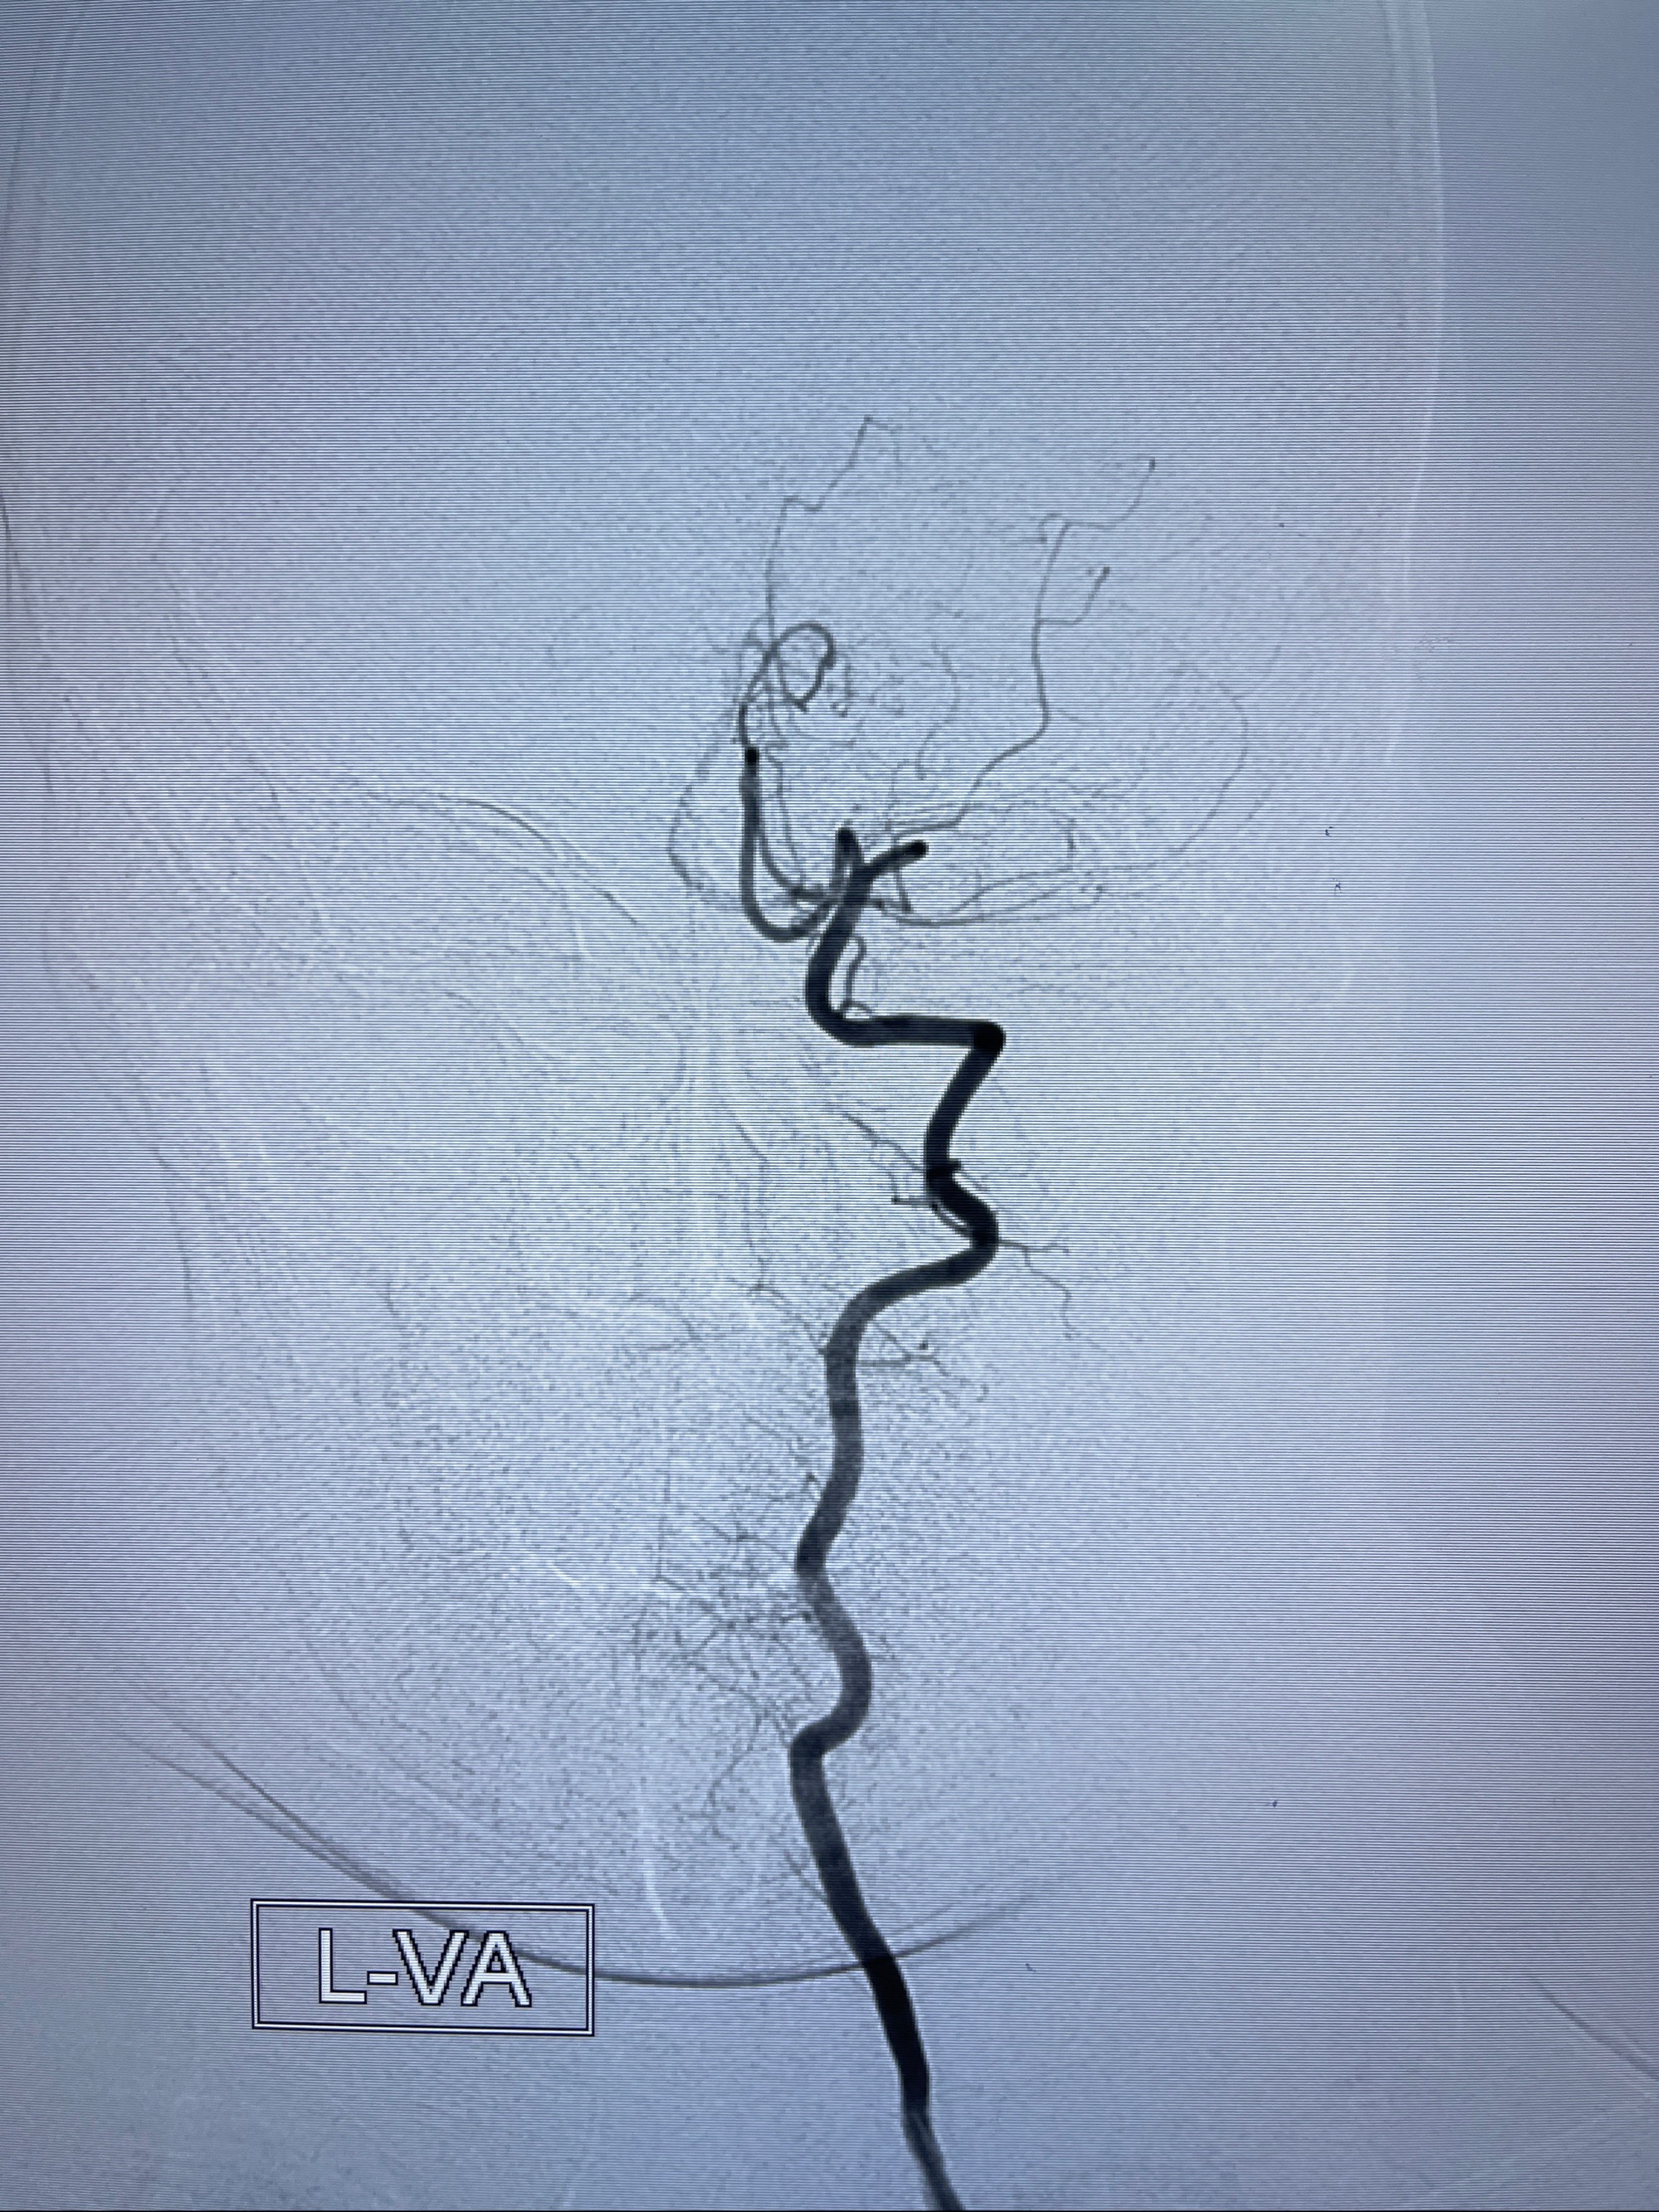

2023年8月21日]景德镇市第一人民医院脑血管造影检查,提示:主动脉弓、双侧颈总动脉、锁骨下动脉造影未见异常,左侧大脑前动脉静脉瘘。

2023-09-13全脑血管造影:前颅底硬脑膜动静脉瘘,供血动脉为双侧胼周动脉、眼动脉脑膜支,静脉向上矢状窦方向引流